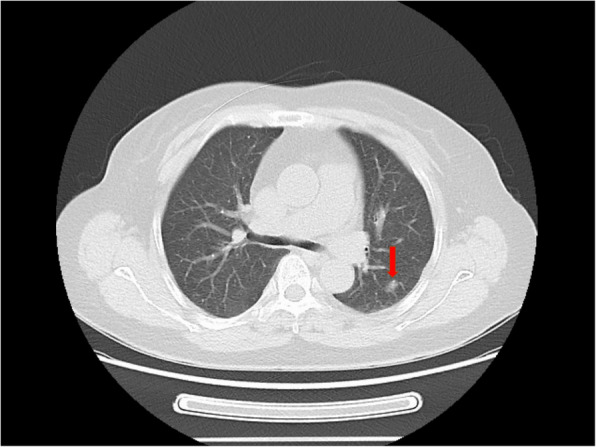

Case presentation: A 68-year-old asymptomatic woman was referred to our institution in June 2022 after a routine health screening revealed a solitary pulmonary nodule. Chest CT demonstrated a 1.2 cm × 0.8 cm hypodense nodular opacity nodule in the posterior segment of the left upper lobe. The lesion remained stable during a 2-month observation period. Despite the absence of respiratory symptoms (e.g., cough, hemoptysis) or constitutional signs (e.g., weight loss), the patient elected surgical resection due to persistent malignancy concerns.